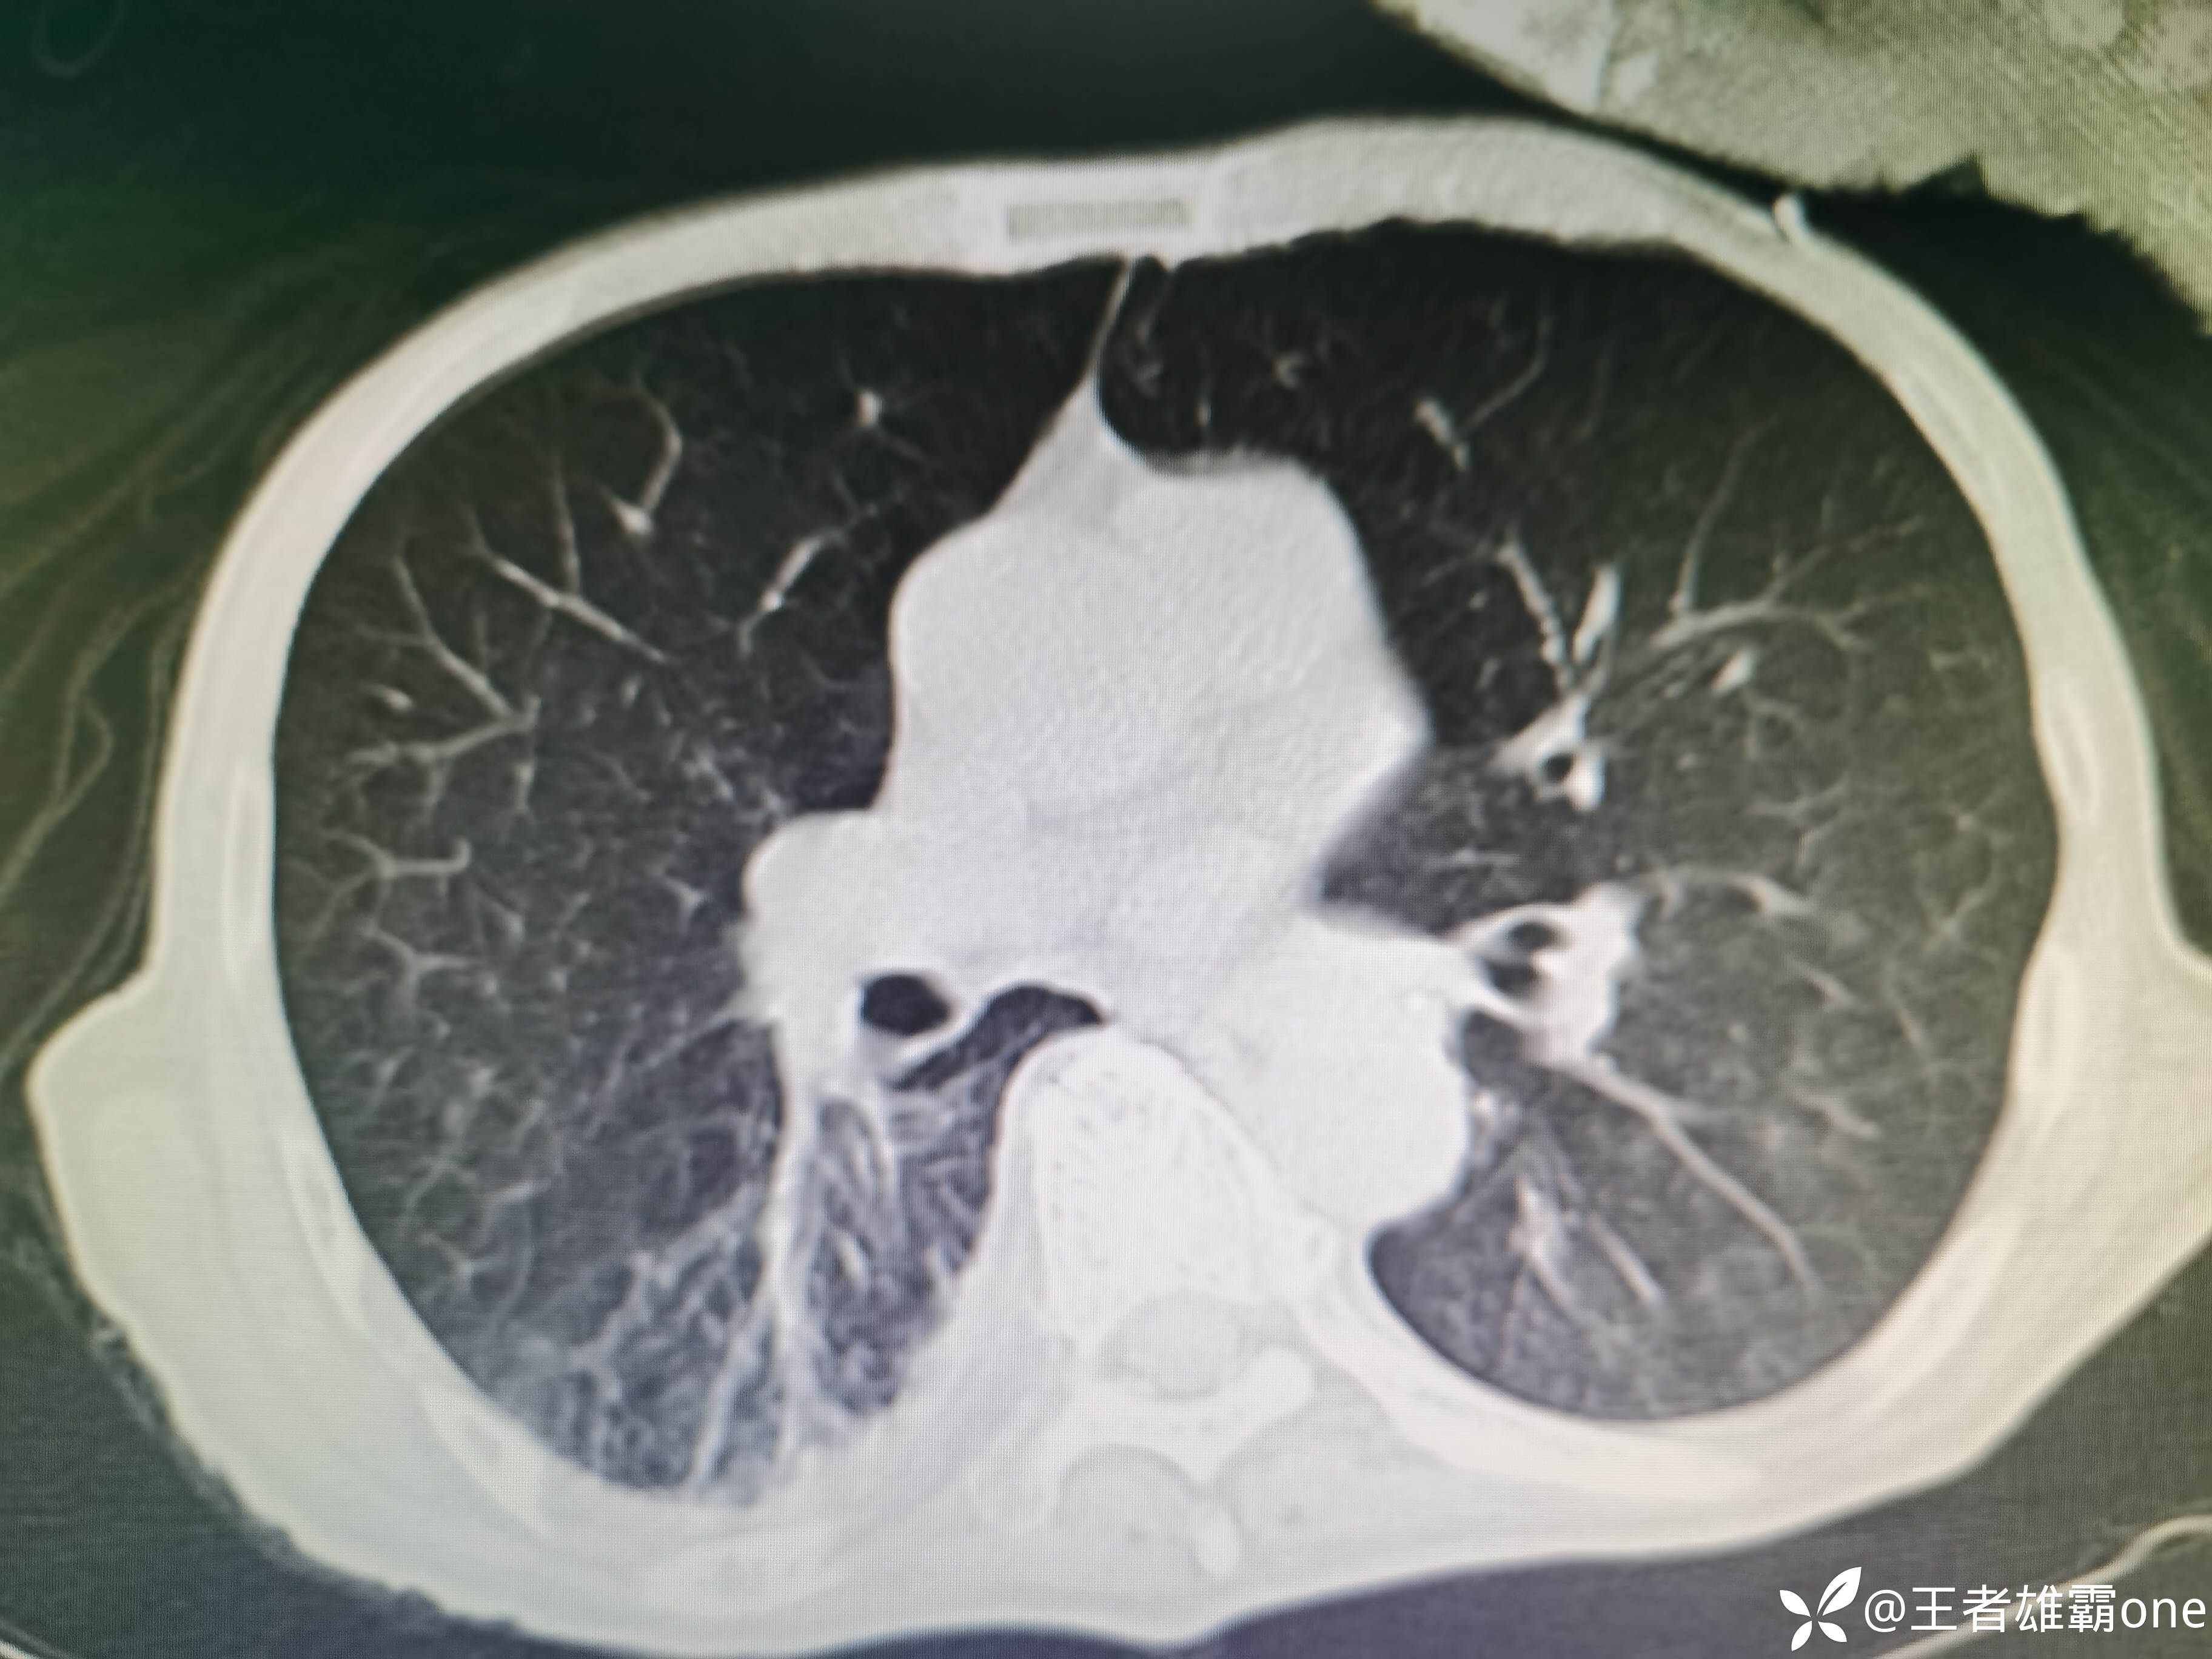

入院时胸部CT:

具体图片: